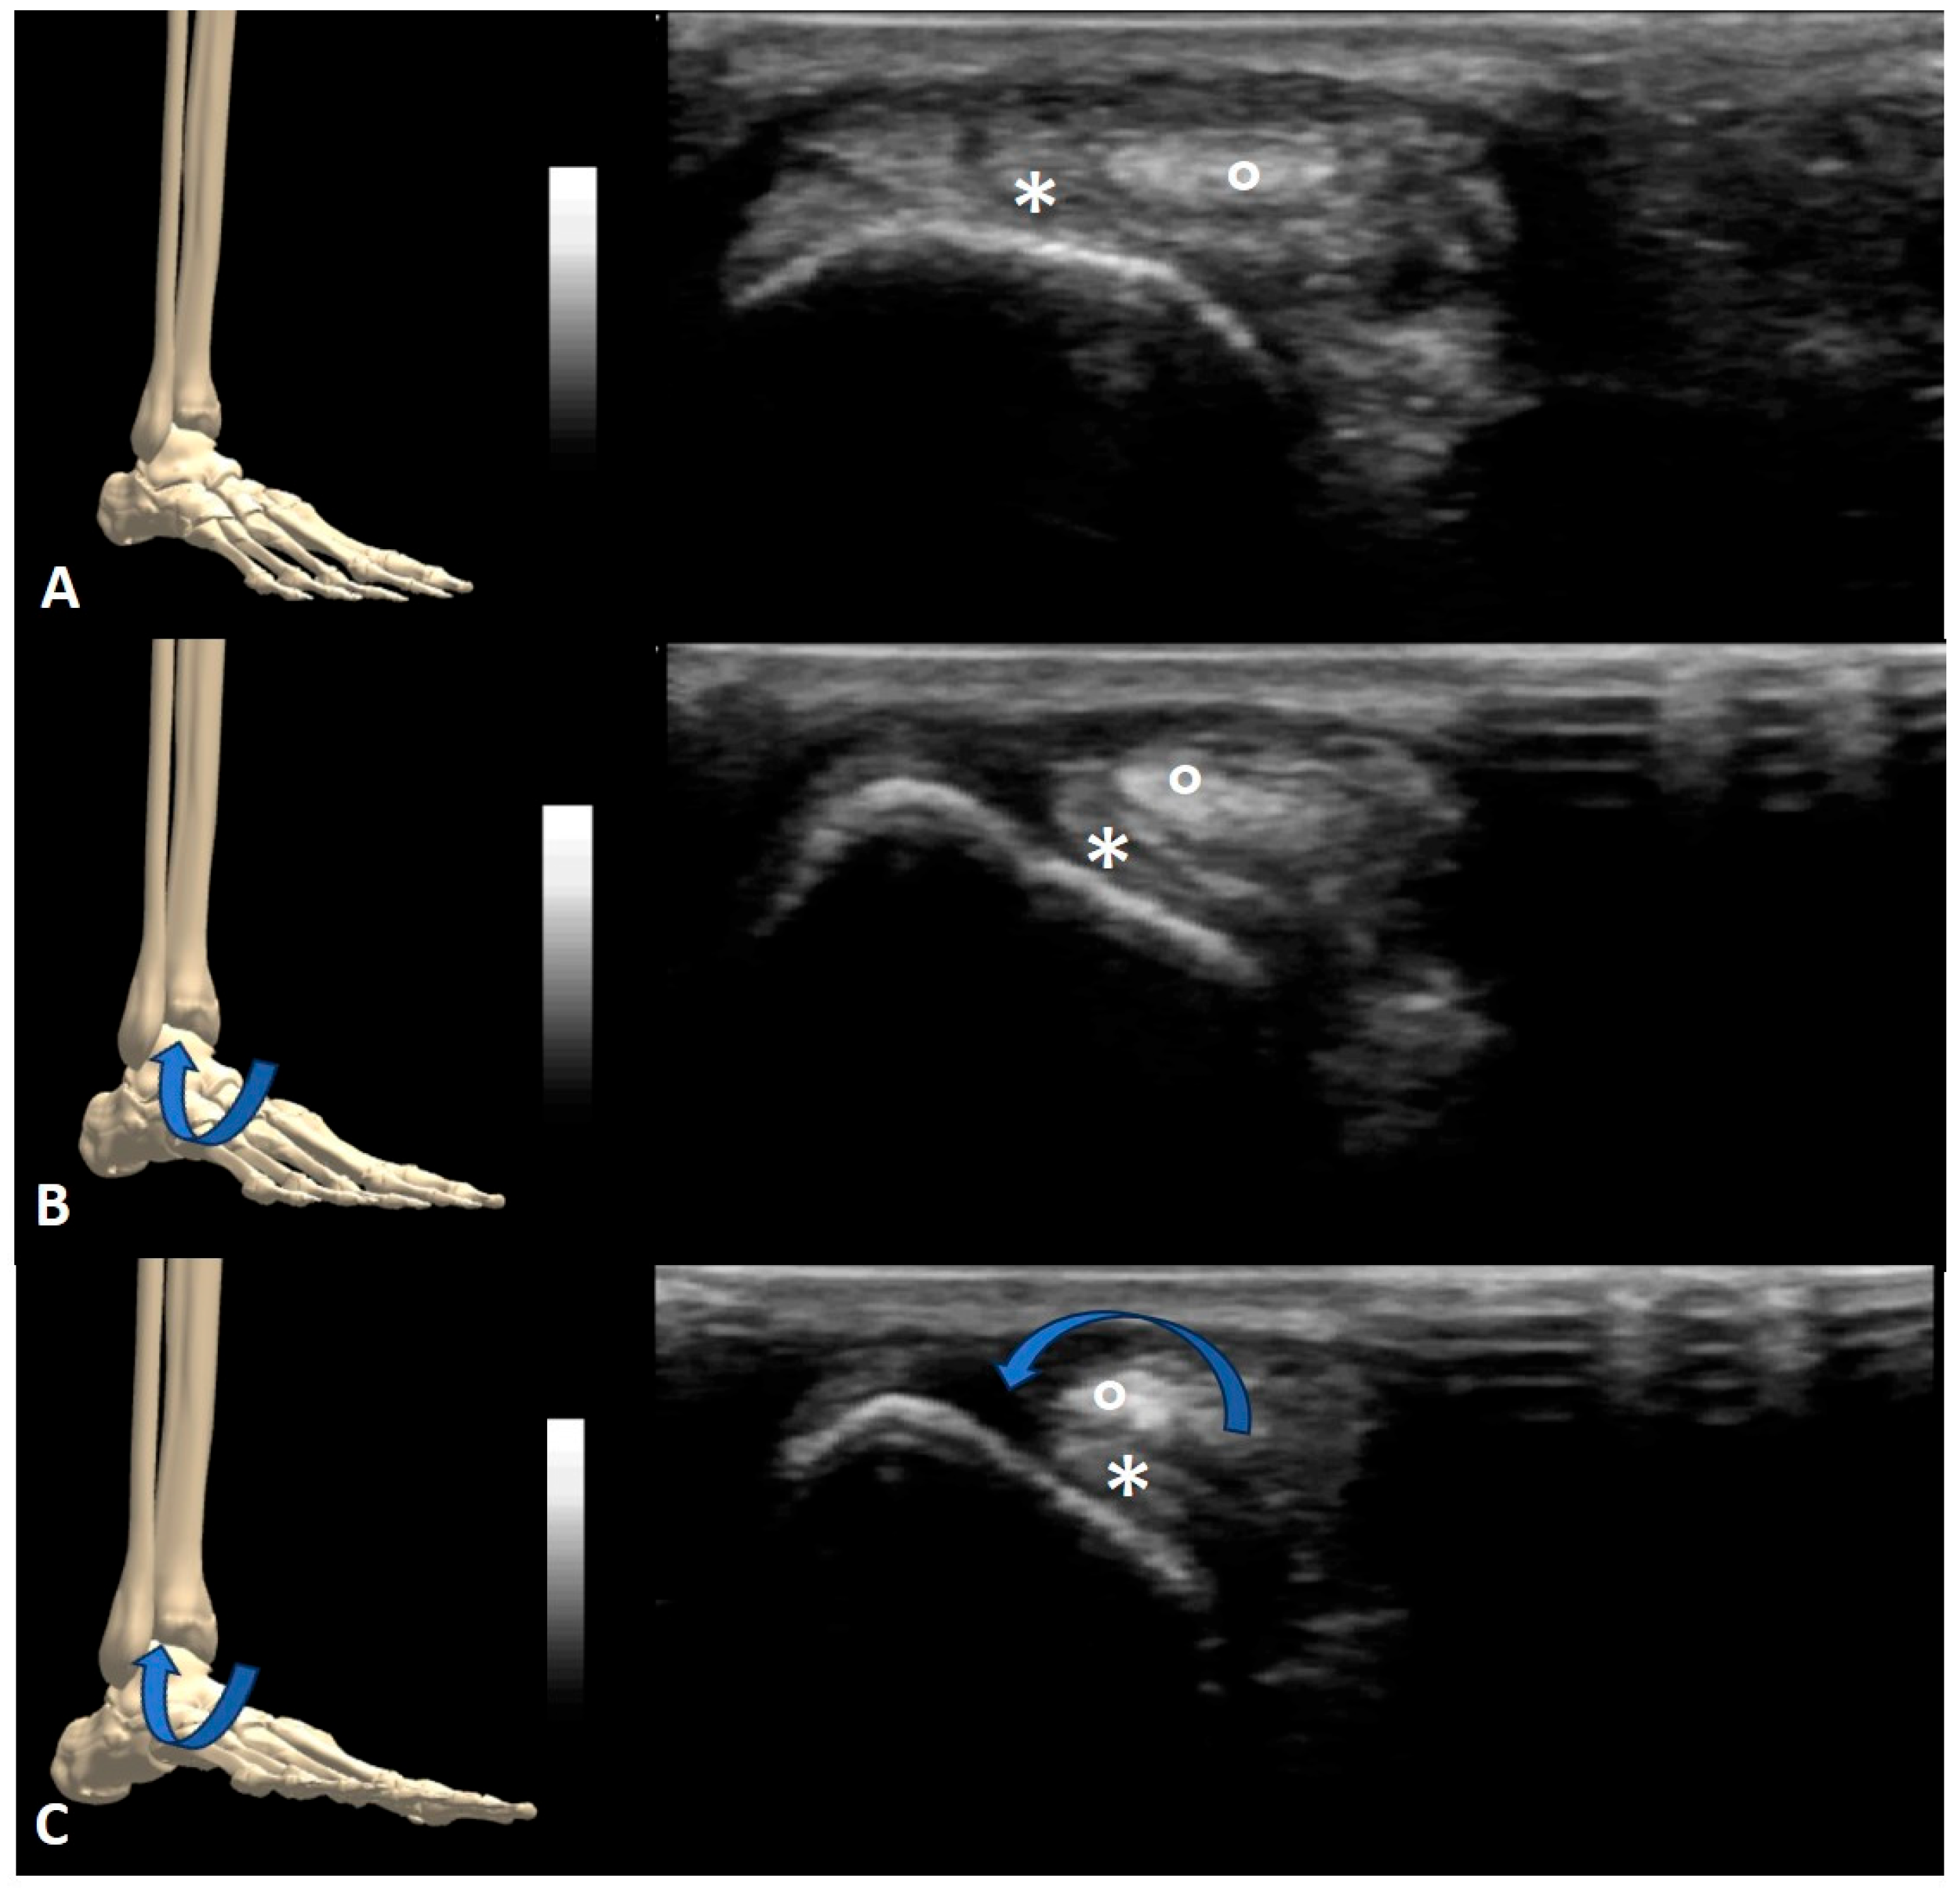

3. Results

4.1. Nerve Snapping

4.2. Tendon Snapping